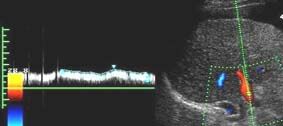

8.Оценка печеночной гемодинамики включает исследование основных сосудов печени - печеночных вен, воротной вены и печеночной артерии, а также их крупных ветвей. Предпочтительно использовать режим ЦДК, позволяющий уточнить не только наличие, но и направление кровотока. Помимо сосудов печени в режиме ультразвуковой ангиографии исследуются круглая связка печени и передняя брюшная стенка - вдоль белой линии живота с использованием линейного датчика, что позволяет более точно выявить наличие кровотока в параумбиликальной вене. ЦДК является высокоинформативным методом в определении обратного (гепатофугального) кровотока в воротной вене и наличия кровотока в порто-кавальных коллатералях. Используя ЦДК, можно быстро определить - является ли визуализируемая трубчатая структура сосудом, оценить наличие и направление кровотока в нем. При ЦДК во внутрипеченочной части воротной вены и в ее ветвях отмечается красный сигнал спектра, соответствующий обычному (гепатопетальному) направлению кровотока при стандартных настройках аппарата. В печеночных венах в норме регистрируется синий сигнал спектра, соответствующий кровотоку от печени, к нижней полой вене и правым отделам сердца.

Определение количественных показателей гемодинамики печени. Больной исследуется в положении лежа на левом боку. Сканирование проводится из доступа через межреберные промежутки (интеркостальный доступ) или из правого подреберья (субкостальный доступ) в зависимости от оптимальной видимости исследуемого сосуда и его хода по отношению к углу инсонации. Задержка дыхания производится больным вне фазы глубокого вдоха или выдоха, что снижает влияние фаз дыхания на характер кровотока в исследуемых сосудах. При определении скоростей кровотока сканирование проводится таким образом, чтобы направление распространения ультразвуковых волн максимально совпадало с продольным ходом сосуда и не превышало 60 градусов по отношению к нему. Величина пробного объема, помещаемого в середину просвета сосуда, составляет приблизительно одну его треть. При измерении таких уголнезависимых величин, как индекс резистентности (RI) и пульсационный индекс (PI), коррекция угла инсонации имеет меньшее значение. При исследовании кровотока во внутрипеченочной части основного ствола воротной вены Nishihara (1994) отметил наилучшие результаты при сканировании из межреберного доступа. Он помещал контрольный объем в основной ствол воротной вены за 1-2 см до ее бифуркации на левую и правую долевые ветви. С учетом данных литературы и своего личного опыта мы считаем указанную выше позицию оптимальной для определения скоростных показателей воротного кровотока (см. рис.).

В норме воротный кровоток имеет типичный венозный спектр, зависящий от фаз дыхания и располагающийся над базовой линией, что соответствует его обычному (гепатопетальному) направлению. Исследование скоростных показателей в основном стволе печеночной артерии проводится в области вертикально направленной части, в точке, наиболее удаленной от бифуркации чревного ствола при сканировании из правого подреберья. В норме скорость кровотока в ней не превышает 60-70 см/сек, RI обычно равен 0,65-0,7.

Визуализация печеночных вен не представляет существенной трудности как из интеркостального, так и из субкостального доступов. При исследовании печеночных вен по методике, предложенной Bolondi (1991), контрольный объем, составлявший 1/3 просвета сосуда, помещается в среднюю печеночную вену на расстоянии 3-6 см от места впадения ее в нижнюю полую вену, что позволяет исключить влияние последней на форму допплеровского спектра. В норме спектр кровотока в печеночных венах трехфазный и зависит от фаз сердечного цикла (см. рис).